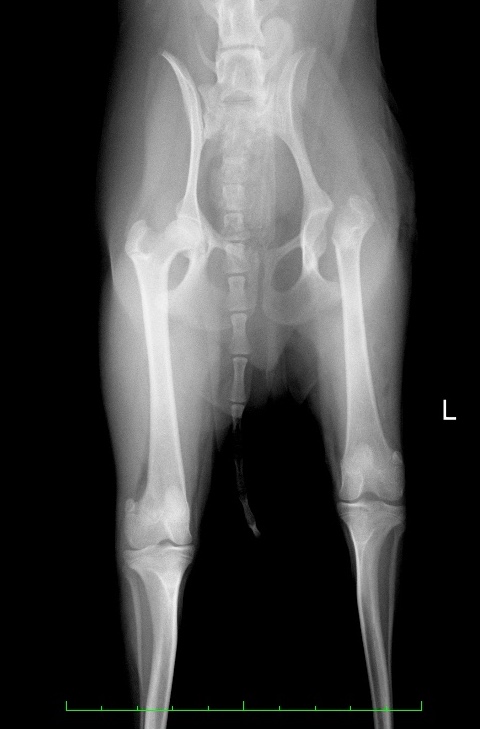

術後のX線写真では痛みの原因になっていた左の大腿骨頭が無くなっているのが分かります。

この部分は股関節の関節構造は無くなってしまいますが、線維組織によって置換されることにより偽関節が形成され、

早い子では術後3ヶ月程度で飼主様から見ても正常肢と見分けが付かないほど機能回復します。

術後X線